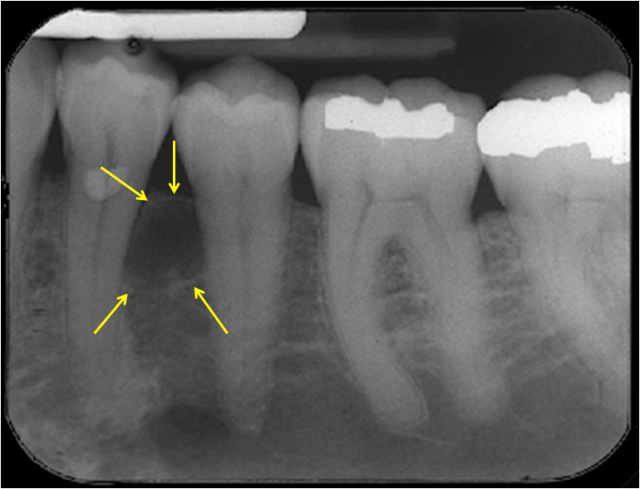

Radicular Cyst Radiology

OPGs are frequently used to identify radicular cysts. The crown of the impacted tooth is involved along with the cystic pericoronal lesion. It projects in the cystic cavity. No imaging tests are further required as it is considered pathognomonic. The additional or primary information is provided with the help of a CT scan and MRI.

It can also help to differentiate a radicular cyst from other lesions which involve the maxilla and mandible. A small size radicular cyst is difficult to identify as it is considered a normal dental follicle. When the crown and dental sac distance expands the normal limit it is known to be the primary sign of radicular cyst.

X-ray and 3D cone beam images can be used to identify the cyst as well. A narrow margin is seen around the radicular cyst. The unilocular shape is commonly seen with these kinds of lesions.